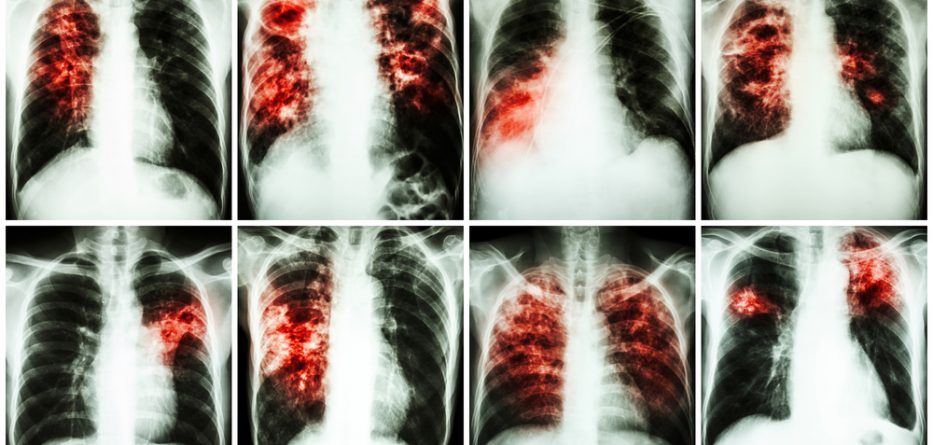

Pulmonary fibrosis is a lung disease that is caused by the scarring of the lungs. With time, the scar tissue may eventually destroy the normal lung tissue, which makes it hard for oxygen to move through the lungs and into the blood. This then leads to shortness of breath, especially when walking and exercising.

Featured image: stockdevil_666 via DepositPhotos